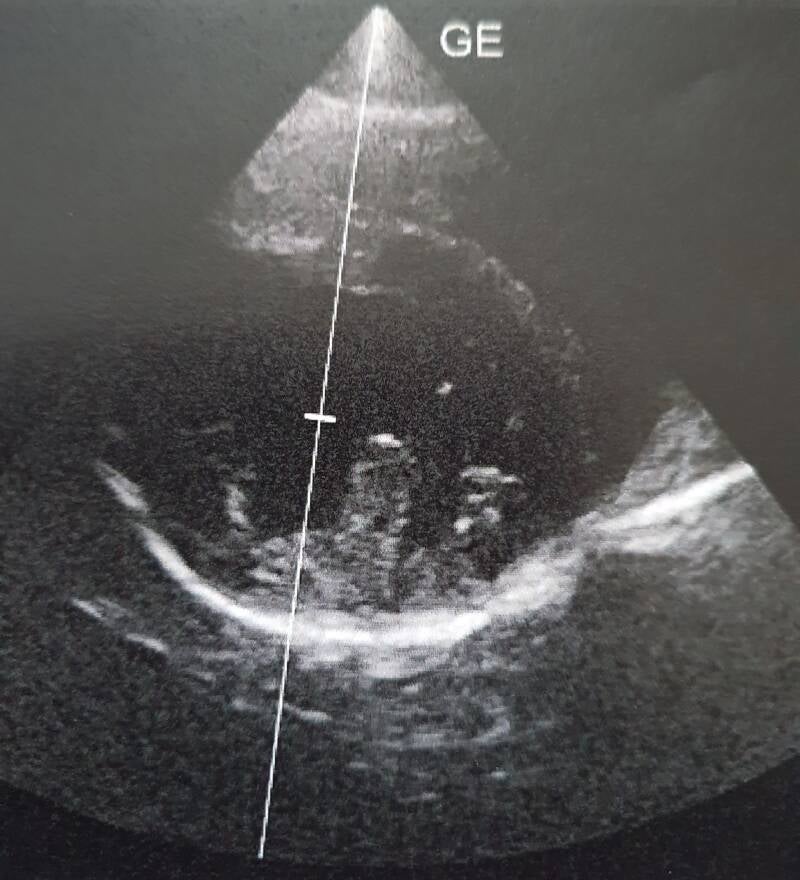

• HCM en PKD doormiddel van een jaarlijkse echo;

HCM is een erfelijke afwijking en is een verdikking in de hartspier wat ernstige gevolgen heeft.

Alleen genen testen is niet genoeg er spelen meer factoren mee die het veroorzaken dan de genen die je kunt testen. Vandaar dat er een jaarlijkse echo gemaakt moet worden om deze erfelijke afwijking te kunnen zien.

Ondanks dat wij deze test uitvoeren wil het niet zeggen dat er nooit wat met het hart van uw kat kan ontstaan.

Helaas geven deze testen nog geen 100 procent garantie daar op in verband met dat ze nog niet op de hoogte zijn welke genen er allemaal mee spelen om het toch te laten ontstaan.

PKD:

PKD is een erfelijke afwijking in de nieren waarbij in beide nieren cysten met vocht gevulde holten aanwezig zijn en groeien naarmate een kat ouder wordt.

ook hier geld weer alleen genen is niet voldoende om deze afwijking te kunnen testen.

vandaar dat er een jaarlijkse echo gemaakt moet worden om deze erfelijke afwijking te kunnen zien.

HCM en PKD screening: MobiDierenarts Harderwijk.